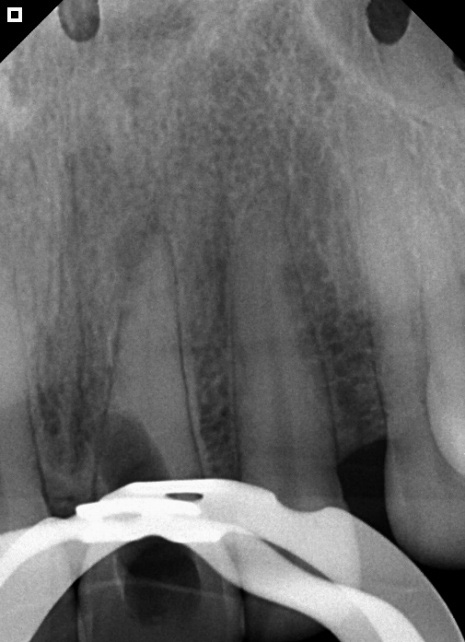

In the second session, absolute isolation was achieved using a rubber dam. The area was irrigated with 2.5% sodium hypochlorite. The canal was located, instrumented, and filled with gutta-percha and Bio-C Sealer bioceramic cement (Angelus) (Figure 3A). The treatment was performed with the aid of an operating microscope to obtain magnification (Figure 3B).

Figure 3: Cement sealer (A)

Figure 3: Radiograph after completion of root canal filling (B)